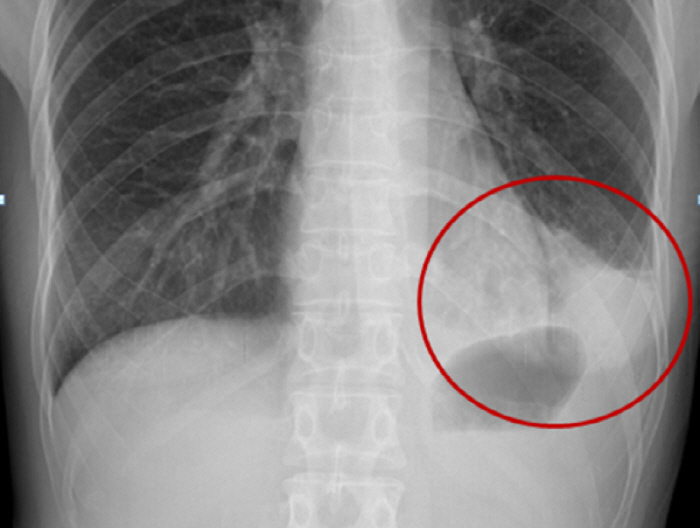

폐렴은 임상적인 증상과 X-선 검사를 통해 진단하게 된다. 폐렴으로 진단된 후의 진료에서 가장 중요한 결정 중의 하나는 입원 여부의 결정이다. 환자의 중증도나 사망 위험도에 따라 적절하게 외래 치료 혹은 입원 치료를 결정하여야 하는데 노년층에서는 여러 동반 질환이 있는 경우가 많아 임상적인 안정상태에 도달하는 기간이 길어지므로 젊은 사람에 비해서 긴 회복기간이 필요하게 된다. 따라서 여러 동반 질환이 있는 노년층에서 입원치료 후 퇴원 시점을 결정할 때에는 조기 재활 치료를 포함한 추가적인 조치가 필요한지를 평가해야 한다.